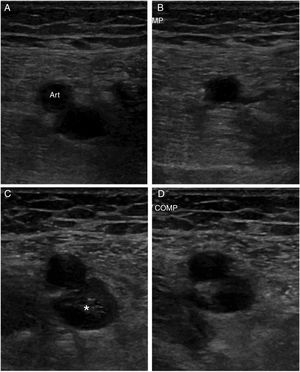

La flebografía se ha considerado históricamente como la técnica de referencia para el diagnóstico de la TVP, pero ahora está en desuso debido a que se trata de una prueba invasiva, dolorosa y no exenta de complicaciones. En la actualidad existe un amplio consenso en que la primera prueba ante la sospecha de una TVP es la ecografía venosa20. El principal criterio diagnóstico es la falta de compresión del segmento venoso explorado (fig. 1). Es una técnica no invasiva que permite evaluaciones seriadas. Tiene una elevada sensibilidad (94,2%) y especificidad (93,8%) para el diagnóstico de TVP proximal en las extremidades inferiores, aunque su sensibilidad disminuye de forma considerable cuando se trata de TVP distal (63,5%)21 o en pacientes asintomáticos (59%)22. Otra limitación es la evaluación de segmentos venosos no compresibles, como las venas ilíacas o el segmento proximal de la vena subclavia en las extremidades superiores. La adición del sistema doppler-color no mejora el rendimiento diagnóstico de la prueba cuando se trata de una TVP proximal, pero es útil en la identificación de las venas distales de la extremidad inferior, así como en la evaluación de venas no compresibles. Además, ayuda a caracterizar mejor el tipo de trombosis al diferenciar entre oclusión total o parcial20. Por otro lado, no hay un consenso tan claro sobre la necesidad de una ecografía proximal (hasta el hueco poplíteo) o completa de toda la extremidad. La primera modalidad no permite diagnosticar TVP distales, por ello, en pacientes con alta o intermedia probabilidad clínica y DD positivo se recomienda repetir la exploración a los 5 o 7 días para descartar una progresión proximal, si una TVP distal pasó desapercibida12,13 y no existe un diagnóstico alternativo más probable. Esta progresión proximal de la trombosis ha sido reportada en alrededor de un 9% de los casos23. Una exploración completa de la extremidad requiere más tiempo y de personal más experimentado. Estudios previos han demostrado que el riesgo de episodios tromboembólicos venosos a los 3 meses de seguimiento sin anticoagulación es muy bajo (0,57%) tras una primera exploración negativa24 y que ambas modalidades son equivalentes en pacientes no hospitalizados con sospecha de TVP en las extremidades inferiores25. Si se opta por esta segunda modalidad y es normal, no serían necesarias exploraciones seriadas12,13. Sin embargo, si se diagnostica una TVP distal aislada, muchas veces su significado clínico es incierto y puede conducir a un tratamiento innecesario. De todas formas, un reciente metaanálisis demostró que la anticoagulación de la TVP distal aislada reducía el riesgo de recurrencias tromboembólicas venosas y la incidencia de embolia pulmonar, sin un incremento significativo del riesgo de sangrado grave26. En el último documento de consenso de la Sociedad Americana de Radiólogos, en ecografía27 se recomienda la realización de una primera ecografía completa con doppler-color de la toda la extremidad. Para evitar tratamientos innecesarios tras el diagnóstico de una TVP distal aislada, recomiendan repetir la exploración a los 7 días y solo tratar si se observa progresión proximal de la trombosis. Si no se observan cambios, recomiendan su repetición a las 2semanas. Si se ha resuelto o no hay progresión, no son necesarias nuevas exploraciones. En este sentido The American College of Chest Physicians en su última revisión de 2016 recomienda controles ecográficos seriados durante 2semanas solo si los síntomas no son graves o no hay factores de riesgo de extensión proximal; en caso contrario, recomienda iniciar anticoagulación de forma similar a la TVP proximal28.

A) Vena femoral normal sin compresión. B) Vena femoral normal con compresión, que la colapsa completamente. C) Imagen de trombosis venosa con material ecogénico en el interior de la vena. D) Falta de compresibilidad. Fuente: Imagen obtenida de Neddleman et al.27.